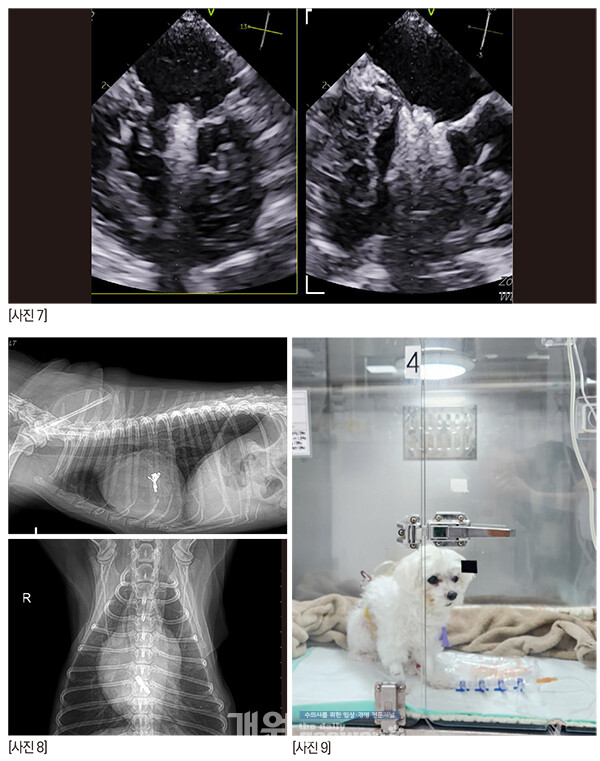

그래서 TEE 를봤다.

zone 2의 스틸컷이다. 어때 보이는가? 잘 닫히고 괜찮은가?

anterior leaflet의 끝단이 flail 되고 있다. 늘상 만나는 심각한 수준의 아이들 보다는 좀 낫긴 한데, 퇴행성 변화로 판막의 끝단이 너덜거리고, anterior leaflet의 건삭은 조금씩 닳아서 끊어지고 있나보다. 끝단이 좌심방을 향해 있다.

anterior의 zone 2-3과 posterior의 zone 2가 좀 뒤집어지고 있다. 이것은 건삭의 일부가 끊어져 너덜거리는 것으로 예측한다. 2D에서는 역류가 심해 보이지 않았지만 3D에서는 꽤 심해 보인다.